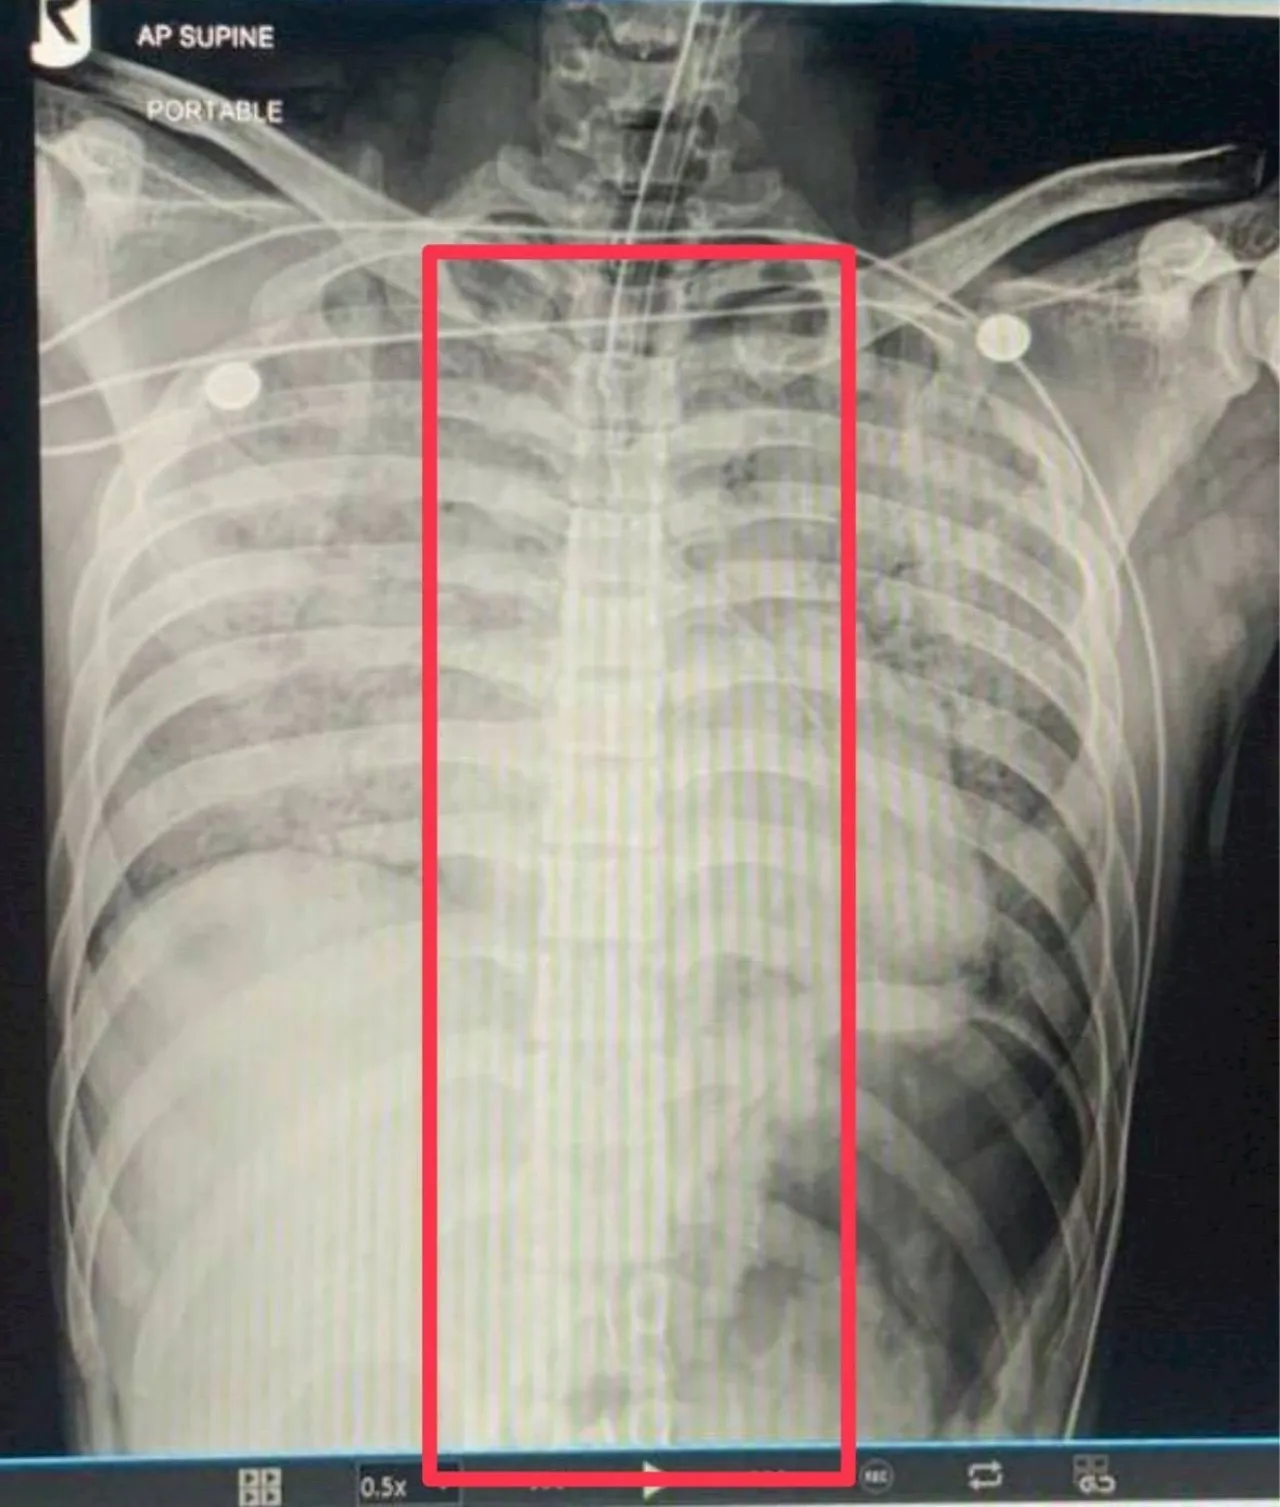

สำหรับประเด็นที่สังคมออนไลน์ตั้งข้อสงสัยอย่างหนักเรื่องการพบ “ช้อนสั้น” ในกระดูกหรือร่างกายของผู้ตายนั้น ผบ.เรือนจำ มทบ.12 ได้ปฏิเสธอย่างหนักแน่น พร้อมยืนยันด้วยหลักฐานทางการแพทย์

“ส่วนตัวผมไม่ทราบเลยว่าประเด็นเรื่องช้อนหลุดออกมาได้อย่างไร เพราะเท่าที่ทราบจากกระบวนการผ่าพิสูจน์และ ฟิล์มเอกซเรย์ของทางโรงพยาบาล ไม่ปรากฏว่ามี ‘ช้อน’ อยู่ในร่างกายของผู้เสียชีวิตแต่อย่างใด“

นอกจากนี้ ผลการชันสูตรเบื้องต้นยังระบุชัดเจนว่า ร่างกายของผู้เสียชีวิตไม่มีร่องรอยการถูกทำร้าย ซึ่งสอดคล้องกับการชี้แจงของโฆษกกองทัพบกก่อนหน้านี้ 🏥